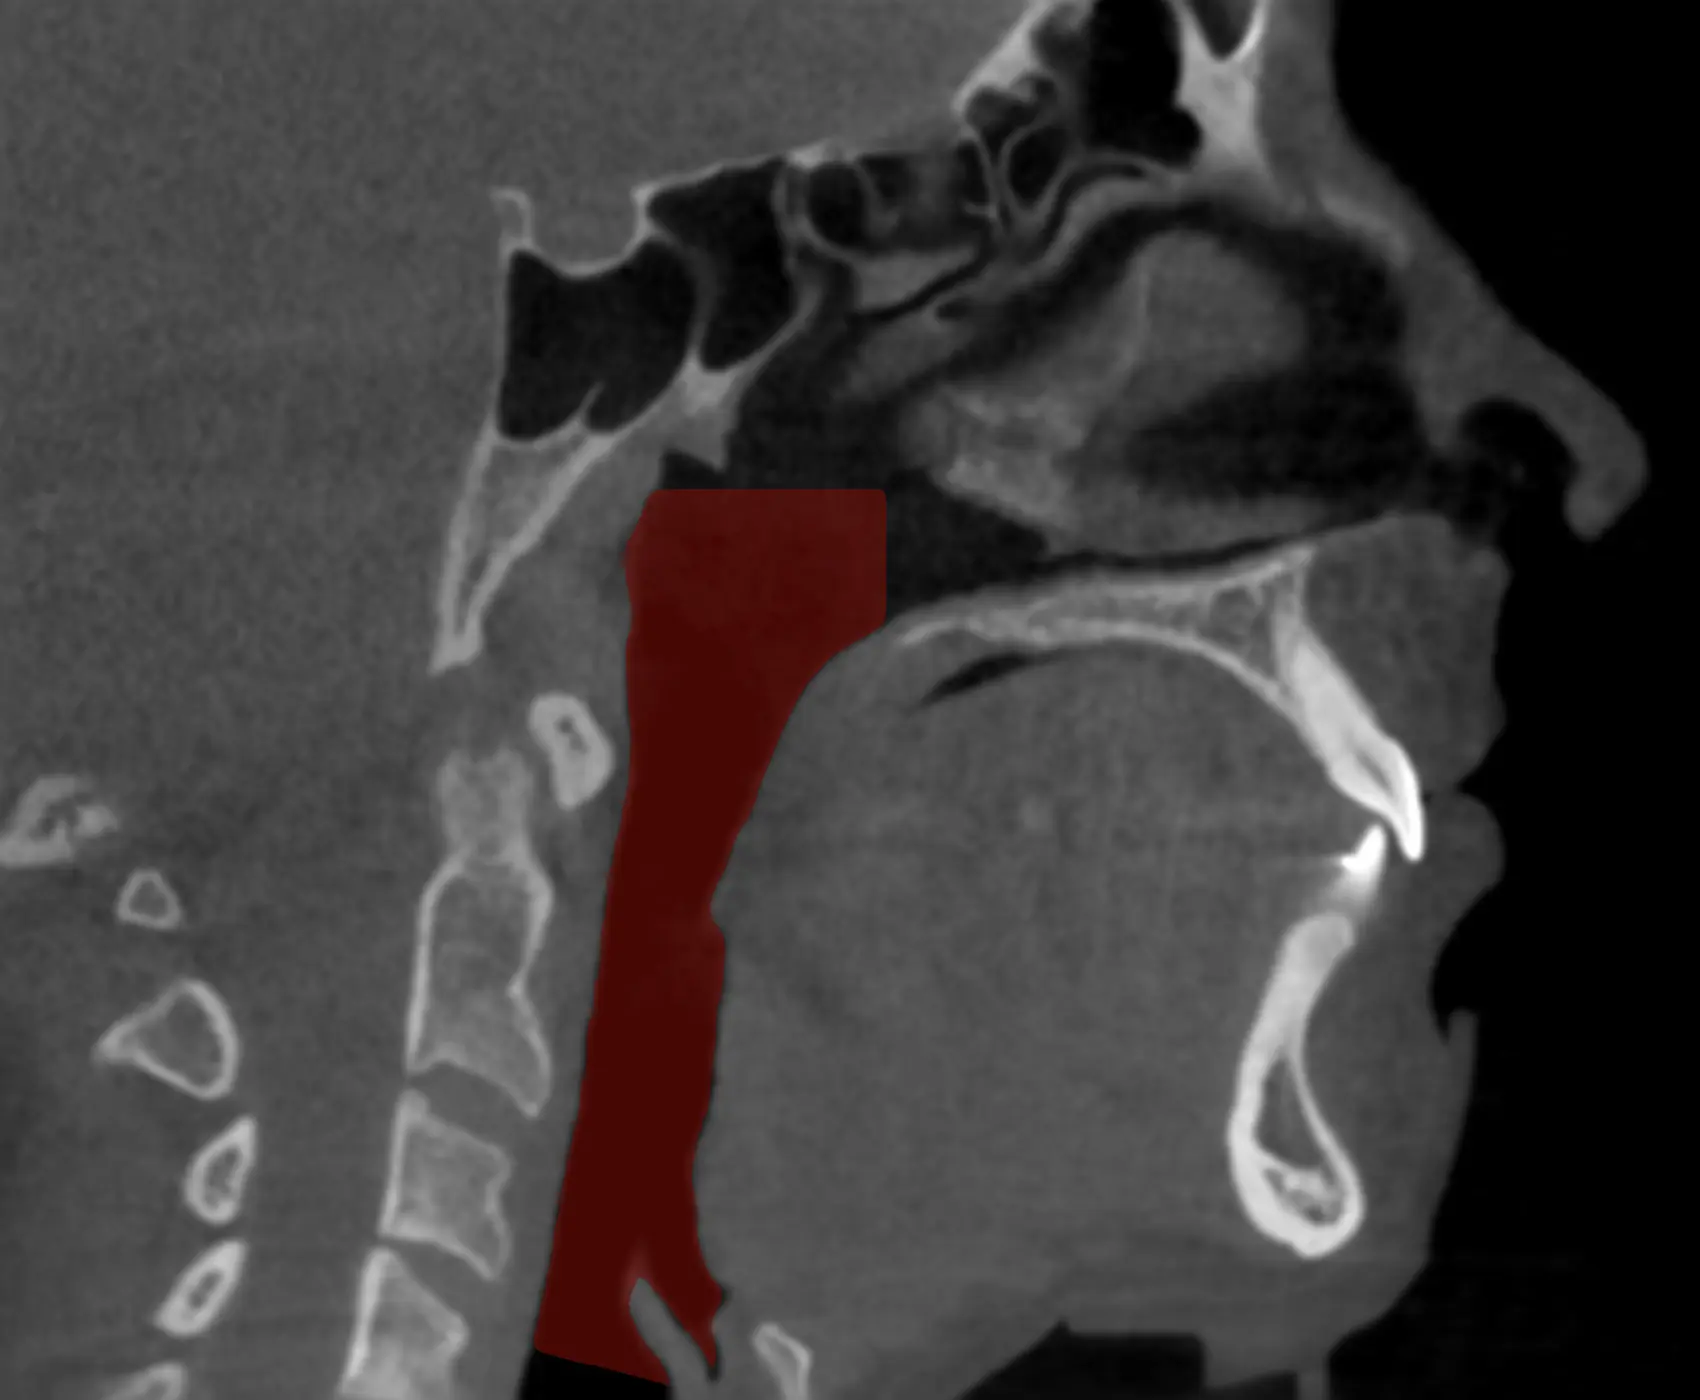

Il est important de noter que la chirurgie n'est généralement pas la première option de traitement pour l'AOS et est souvent considérée lorsque d'autres traitements, tels que la ventilation spontanée avec pression expiratoire positive (CPAP) ou les dispositifs d'avancement mandibulaire, n'ont pas été efficaces ou tolérés. Avant de recommander une intervention chirurgicale, le chirurgien maxillo-facial effectuera une évaluation minutieuse de votre condition ainsi que de votre profil squelettique afin de déterminer si vous êtes effectivement candidat à la chirurgie. Bien souvent une anomalie ou un manque de projection des mâchoires peut avoir un impact significatif sur le volume des voies respiratoires supérieures. Un avancement maxillo-mandibulaire peut dès lors être considéré. Cette chirurgie pratiquée par les chirurgiens maxillo-faciaux améliore significativement les dimensions et la stabilité des voies aériennes pharyngées en plus d'être associée à un repositionnement antérieur des muscles suprahyoïdiens. L'analyse des changements morphologiques à l'aide d'une tomodensitométrie après la chirurgie d'avancement du complexe maxillo-mandibulaire montre un élargissement significatif des dimensions latérale et antéro-postérieure des voies respiratoires pour une grande majorité de patients.